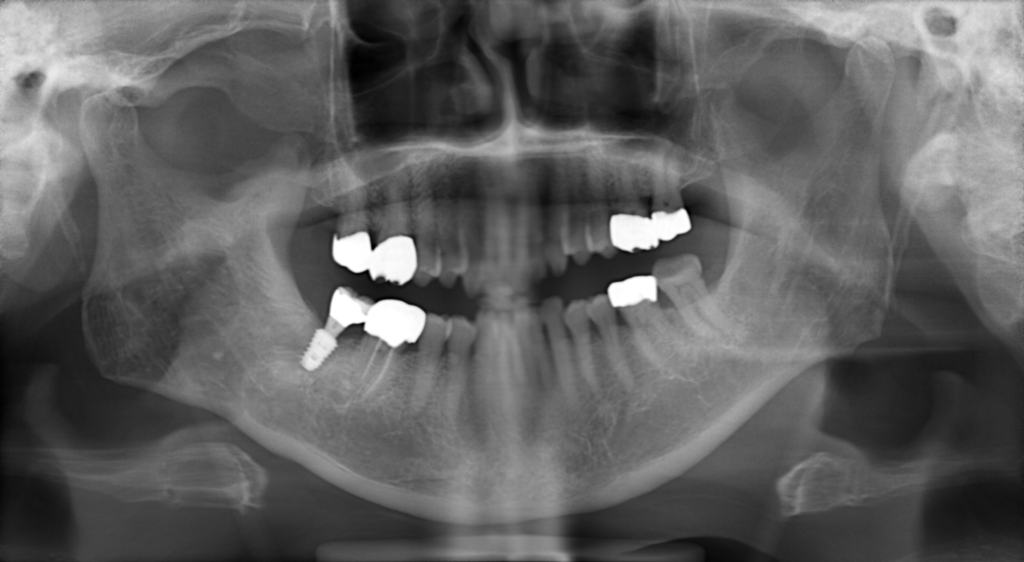

N様 40代 男性 インプラント実例 #40

右下奥歯がなくなってしまったということて、噛みにくいので、歯が欲しいということで、来院されました。骨が少なかったため、インプラントを埋入する際に骨を作り、埋入のオペを行いました。少し時間(3ヶ月をおいて)骨ができていることを確認して、被せ物を入れました。被せ物はセラミックで作っています。

治療前

治療後